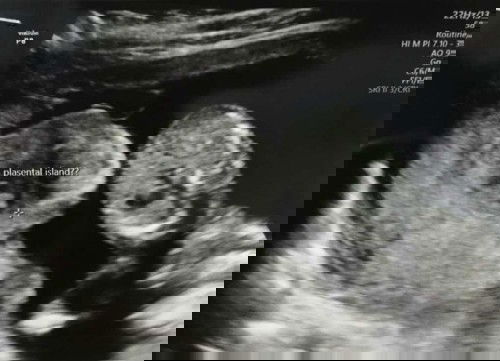

bentuk placenta uk 15w

bunda . saya mau tanya jika ada yg tau atau mungkin pernah mengalami. usia kandungan saya 15mnggu 2hri, ketika usg apakah ada yg tau bentuk placenta sperti ini. dokternya msh blm bisa menjelaskan, dan agar lbih jlas bln dpn di sruh usg fetomaternal. apa ada yg tau ?